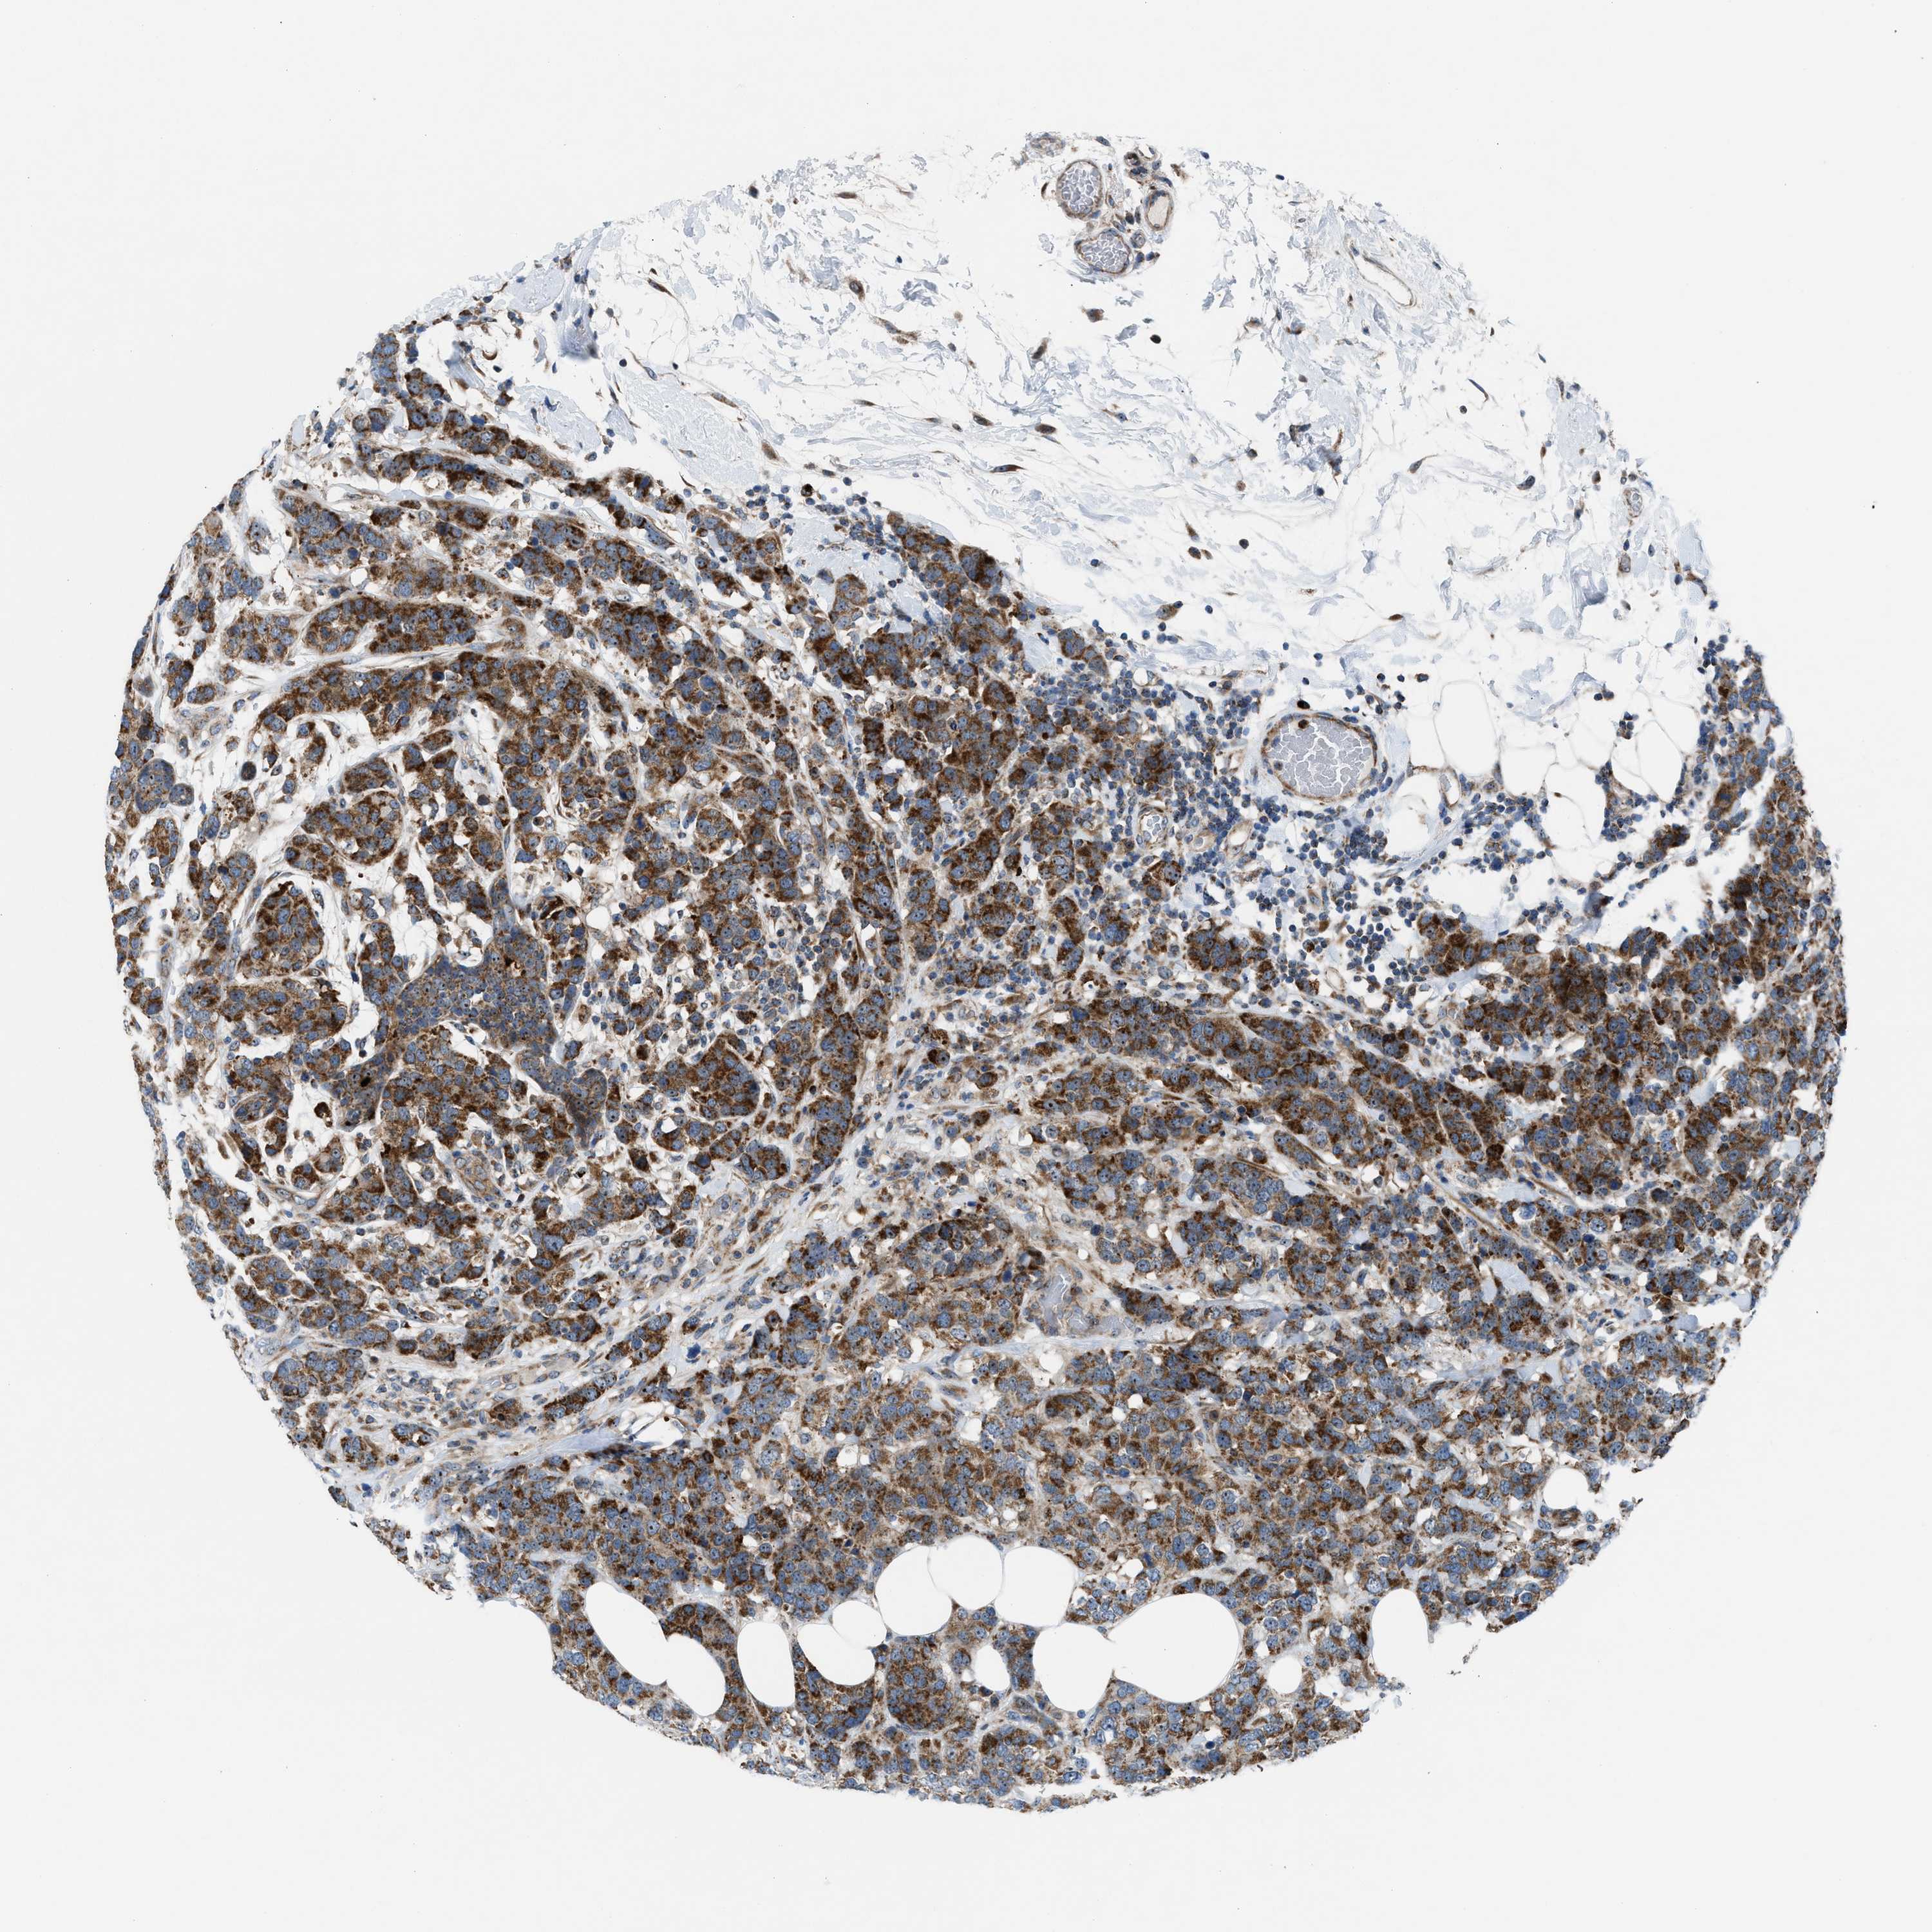

CANCER BREAST CANCER Show tissue menu

BRCA TCGA BRCA VALIDATION PROTEIN EXPRESSION